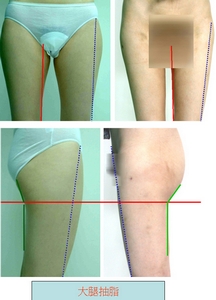

1. 大腿抽脂: 整體變勻稱---大腿圍(膝上60公分處)約瘦4至5cm左右+ 臀圍約瘦4至5cm左右

即使是左圖非常瘦(163cm, 42kg)的女性, 穿越緊身的褲子或裙子, 本來想更顯玲瓏, 沒料到越容易暴露缺點. 手術後3個月, 馬鞍部(也就是大腿外側), 大腿內側(內大腿上方與膝蓋附近), 大腿前方, 臀部下緣都得到完整的抽脂. 抽脂量2700 cc, 體脂肪率下降4%. 手術後因為大腿與小腿寬度接近, 更顯高挑, 更有自信穿超短裙, 不怕"露餡".

即使是左圖非常瘦(163cm, 42kg)的女性, 穿越緊身的褲子或裙子, 本來想更顯玲瓏, 沒料到越容易暴露缺點. 手術後3個月, 馬鞍部(也就是大腿外側), 大腿內側(內大腿上方與膝蓋附近), 大腿前方, 臀部下緣都得到完整的抽脂. 抽脂量2700 cc, 體脂肪率下降4%. 手術後因為大腿與小腿寬度接近, 更顯高挑, 更有自信穿超短裙, 不怕"露餡".